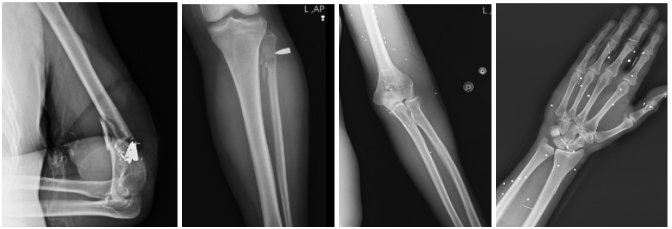

چهار نمونه از آسیبهای لگن، ران و مفصل ران که در سه تصویر با پراکندگی متعدد ساچمههای شاتگان در بافت نرم اطراف لگن و ران همراه است و در یک تصویر، تخریب شدید و شکستگی چندتکه استخوان ران با قطعات فلزی پرانرژی دیده میشود

در دست و پا، توصیف پزشکان بارها بر «شکستگیهای چندتکه» و گاز در بافت نرم بهعنوان الگوی سازگار با آسیب نافذ ناشی از شلیک گلوله تاکید میکند. در اندام فوقانی، چند پرونده شامل خردشدگی شدید استخوان بازو یا اختلال مفصل آرنج است که میتواند با خطر آسیب عصب و عروق همراه باشد و به ناتوانی پایدار مانند ضعف، بیحسی یا فلج دست منجر شود.

شکستگی خردشونده اطراف مفصل آرنج با حضور قطعات فلزی، شکستگیهای دیافیز استخوانهای ساعد با الگوی سازگار با نفوذ پرتابه، و پراکندگی متعدد ساچمهها در دست و مچ